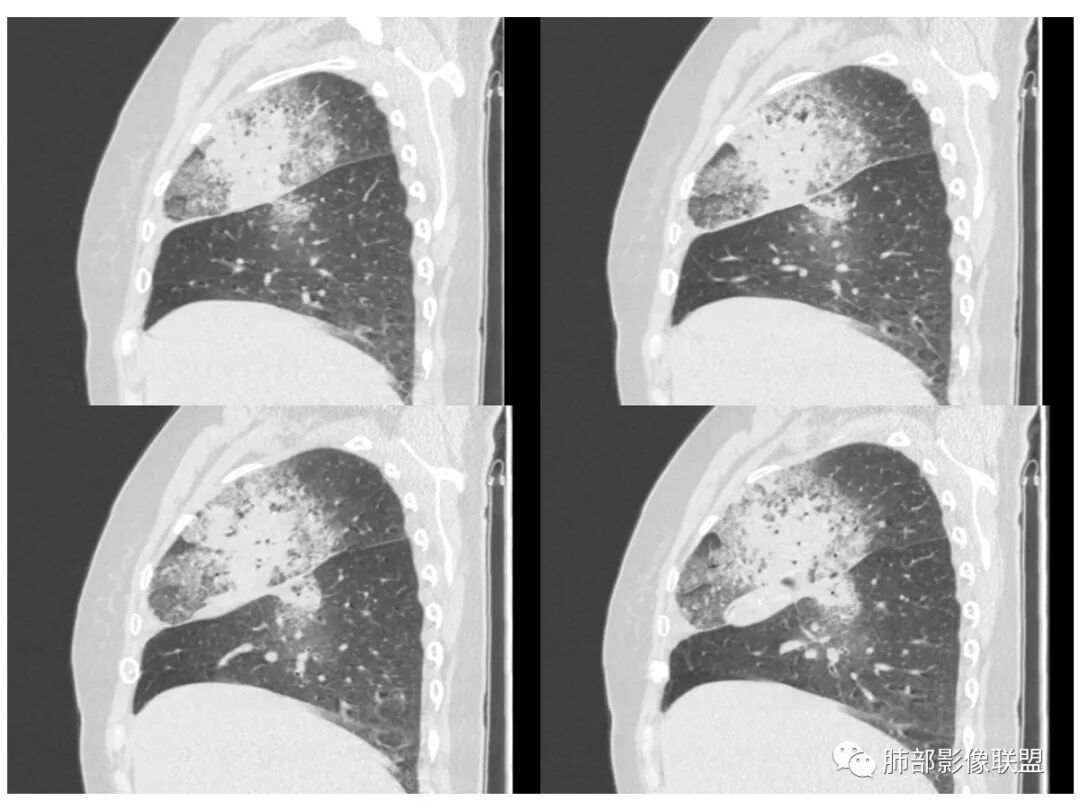

右肺上叶大片状阴影,内见僵硬的支气管,部分支气管轻度扩张,内见一空洞和液平,病灶边缘可见磨玻璃影,首先考虑恶性病变,粘液性腺癌伴感染可能。

老年女性,右肺上叶大片实变及磨玻璃密度影,磨玻璃边缘清晰,内可见小叶间隔增厚,内可见空洞,似可见分隔,叶间裂局部膨隆,纵膈窗,没有增强,枯树枝不明显,肺炎型肺癌可能,鉴别大叶性肺炎,结核?

胸CT:右肺上叶实变内可见支气管充气征,近端支气管狭窄,远端扩张,周围可见毛玻璃影,右肺中叶支气管闭塞,并可见气道壁钙化,右肺中叶体积缩小,实变内可见空洞,并可见气液平面,空洞周围可见毛玻璃样影,右肺下叶支气管开口狭窄,右肺门淋巴结肿大。纵隔窗可见病灶与壁层胸膜间隙增宽,考虑良性病变-----感染性病变------TB?

1.右上肺大片状影,周围有磨玻璃影,支气管截断征、枯枝征、远端支气管充气征,可见多个大小不等囊泡(支气管阻塞活瓣作用形成),病灶有少许收缩力感,叶间裂被稍牵拉内移;

老年女性,慢性病程,咳嗽伴白色粘液痰,无发热腹痛,糖尿病,白细胞及C反应蛋白不高,血沉快,铁蛋白高。胸部CT,右肺上叶大片状实变伴磨玻璃密度影,边界不清,边缘局部膨隆,叶裂弧形下坠,实变影宽基底与胸膜相贴;右肺下叶前基底段见类似病灶;右肺中叶不张并空洞形成,空洞内见气液平面;综合考虑右肺上叶及下叶肺炎型肺癌,右肺中叶结核。

白色粘液痰,枯树枝,支气管僵直,有空洞,磨玻璃,叶间裂膨隆、下坠,吴婧老师的肺炎型粘液性腺癌十大特点中占了好多条,所以考虑粘液腺癌,就差增强看看强化如何,血管如何了

老年女性,咳白色粘液痰,右肺跨叶大片高密度影,密度不均匀,其内见支气管枯树征,有空洞,边缘部分清楚,叶间裂有下坠膨隆感。考虑粘液腺癌,鉴别干酪性肺炎